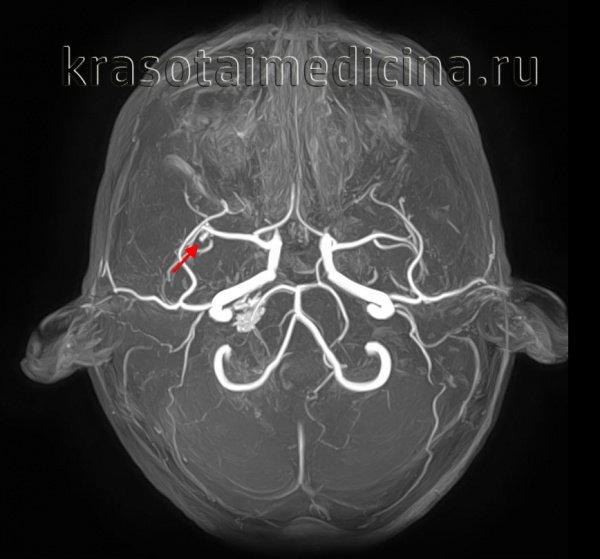

КТ-ангиография головного мозга (3D-реконструкция). Аневризматическое расширение левой средней мозговой артерии